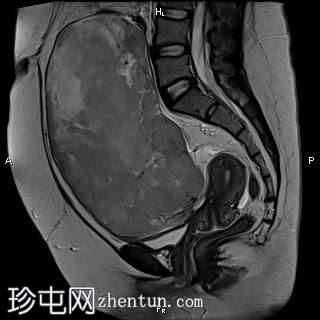

矢状位

T2

盆腔内可见一巨大多分叶实性肿块,内部有隔膜,T2WI信号不均匀,T1WI信号不均匀,呈低信号。肿块内散在分布囊性/坏死性病变。

肿块外可见子宫和右侧卵巢,肿块似源自左侧卵巢。该肿块压迫膀胱和两侧远端输尿管,并导致肠管和血管结构移位,但无侵袭或包裹征象。

造影后,肿块呈不均匀强化,隔膜强化。

远端髂腹旁和两侧髂骨旁区域可见少量肿大淋巴结。